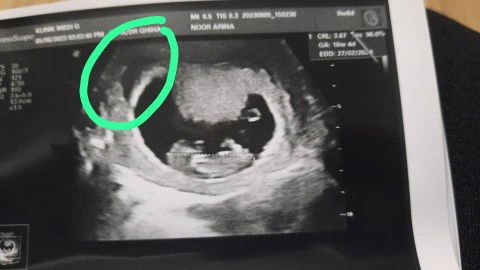

Saya nak double confirm, bolehkan kalau kita checkup di klinik swasta kemudian kita bersalin di hospital kerajaan? Kena buka buku pink kk juga ke? Sebab sekarang dah 34weeks. Takut nanti hospital kerajaan tak terima. Dua anak sebelum ni fully kerajaan #seriusnanya #ingintahu #pleasehelp #bantusharing